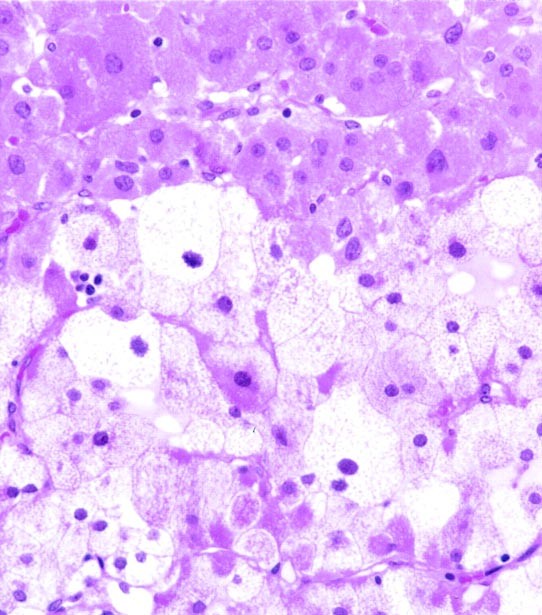

The adrenal glands of all four cases were almost completely replaced by a partially encapsulated neoplasm. Only a thin rim of residual normal adrenal gland remained. The polygonal neoplastic oncocytic cells were seen arranged predominantly in a diffuse pattern (Fig. 2). In some areas, nests and trabeculae of neoplastic cells separated by sinusoids lined by flattened endothelial cells were identified (Fig. 3). Large irregular zones of necrosis were noted. The neoplastic cells were large, round to polygonal, with round nuclei and prominent nucleoli, and abundant granular and eosinophilic cytoplasm (Fig. 4). Giant mononuclear and binucleated cells were seen in one case (case 4). Focal bizarre cytologic atypia was noted in the remaining three cases. Clusters of neoplastic cells with foamy cytoplasm were noted in two tumors (Fig. 5). There were rare mitotic figures (less than one per 10 high power fields). Vascular invasion, outside of the tumors, was identified in two cases and extra capsular extension in three tumors.